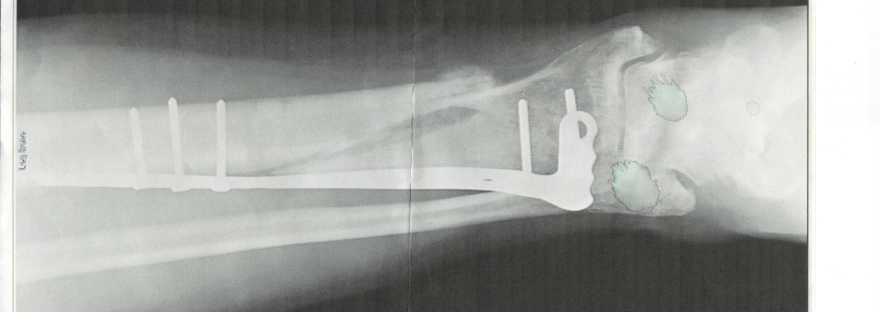

Greg has a BIG scar on his calf. Several years ago he was riding through the woods on a dirt bike when his confidence and his abilities no longer matched and he crashed. Fortunately the guy he was riding with was able to call 9-11. The spiral fracture of his tibia resulted in surgery with pins and screws. He bemoans how well that scar healed, “Dudes need at least one good scar. They’re manly!”